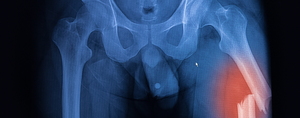

노년기 고관절 골절 환자 중 인지기능 저하와 근감소증을 동시에 앓고 있는 경우, 수술 후 1년이 지나도 절반 이상이 독립적인 보행을 회복하지 못하는 것으로 나타났다. 초고령 사회로 접어든 지금, 고관절 골절 후 재활치료에 있어 단순한 근력 회복 중심 접근에서 벗어나 인지 기능까지 고려한 다차원적 치료 전략의 필요성이 제기된다.분당서울대병원 재활의학과 임재영 교수, 순천향대천안병원 재활의학과 임승규 교수 공동 연구팀은 인지기능 저하와 근감소증의 동반 여부에 따른 보행 회복률을 분석해 노인의학 분야 국제학술지 (Journal of Ge

고관절 골절 치료 후 재활에는 통상적인 방법보다는 통합프로그램이 효과적이라는 연구결과가 나왔다. 통합프로그램(Fragility Fracture Integrated Rehabilitation Management, FIRM))에는 장·단기 재활 계획으로 물리치료, 작업치료, 낙상방지교육, 퇴원 후 관리, 지역사회 연계 등을 포함한다.분당서울대병원 재활의학과 임재영 교수팀은 골절 환자가 보행능력을 포함해 일상생활에서 운동 기능과 삶의 질을 높이고 사망률을 낮출 수 있는 FIRM을 개발하고, 효과를 확인했다고 노인의학 분야 학술지(Jour